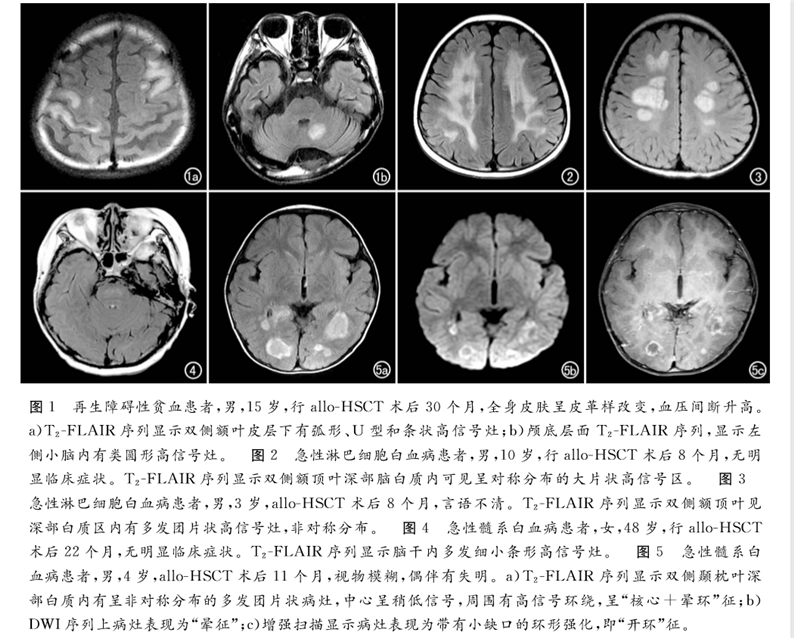

論文回顧性分析了2013年6月—2017年12月北京陸道培醫(yī)院確診為allo-HSCT后并發(fā)中樞神經(jīng)系統(tǒng)慢性移植物抗宿主病的12例血液病患者的臨床和影像學(xué)資料。得出結(jié)論,MRI是發(fā)現(xiàn)血液病異基因造血干細(xì)胞移植(allo-HSCT)后并發(fā)中樞神經(jīng)系統(tǒng)慢性移植物抗宿主病的有效手段,可以提高對本病的診斷及鑒別水平,為臨床制訂佳治療方案提供幫助。